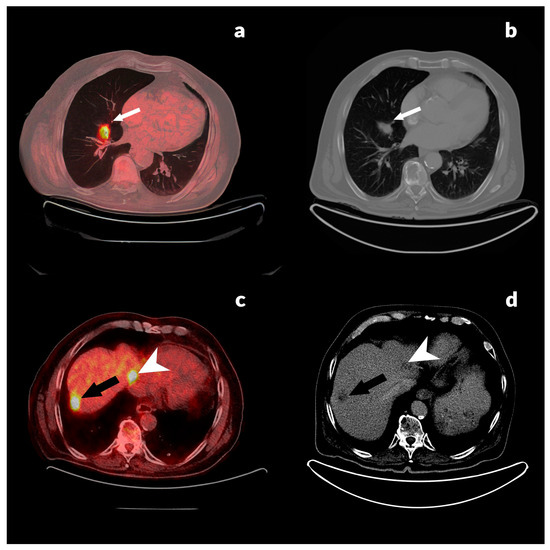

3.2.3. Case Reports